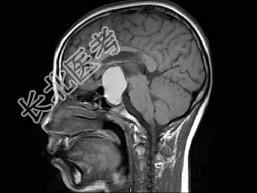

- 单项选择题男,19岁, 视力模糊1周,MRI检查如图所示应诊断为 ( )

A、颅咽管瘤

B、脑膜瘤

C、垂体瘤卒中

D、脑膜膨出

E、未见异常